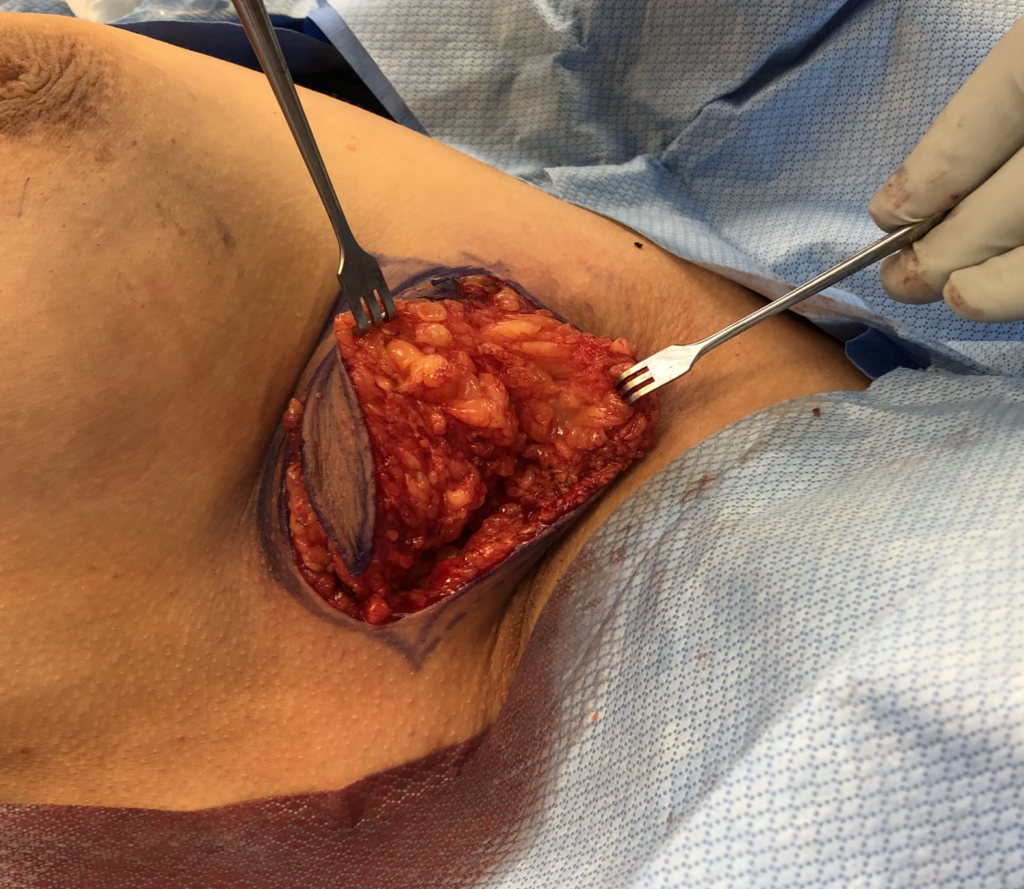

The video below demonstrates removal of a phyllodes lesion during lactation. There are several things to learn from this video:

- Breast imaging, breast biopsy, and breast surgery are safe during pregnancy and lactation. In fact, it would have been more ideal to remove this mass during pregnancy (before it grew and to rule out anything worrisome like a malignant phyllodes tumor). It also is far easier to operate without complication on a pregnant, rather than lactating, breast.

- In retrospect, this patient would have benefitted from a drain post-operatively rather than repeated aspirations.

- Breastmilk is under autocrine (local – i.e. the breasts function independently) control after two weeks postpartum (the first two weeks are endocrine, or central control). This means you can upregulate and downregulate the breasts independently.

- It is very important to treat hyperlactation (overproduction of breastmilk) in general, as well is when it is present when a patient requires surgery.